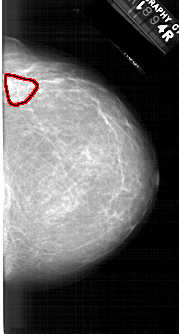

A_1610_1.LEFT_CC

RIGHT_CC LINES 6001 PIXELS_PER_LINE 3211 BITS_PER_PIXEL 12 RESOLUTION 43.5 OVERLAY

FILE: A_1610_1.RIGHT_CC.OVERLAY

TOTAL_ABNORMALITIES 1

ABNORMALITY 1

LESION_TYPE MASS SHAPE ASYMMETRIC_BREAST_TISSUE MARGINS ILL_DEFINED

ASSESSMENT 4

SUBTLETY 3

PATHOLOGY BENIGN

TOTAL_OUTLINES 1

BOUNDARY